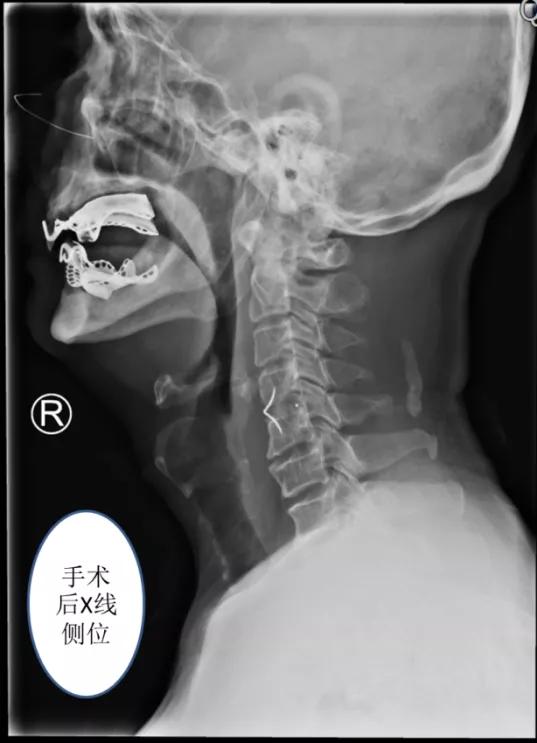

最终凭借丰富的颈椎前路手术经验和娴熟的操作,王德春主任团队根据综合评估,制定了“颈椎前路骨赘切除+零切迹融合器颈椎融合”手术方案。

术中见患者颈椎前方骨赘巨大,凸起处成鸟嘴状,将颈椎前方骨赘磨除干净,然后零切迹融合器行颈56节段融合手术。手术用时仅1个多小时,出血极少,术后第二天病人就佩戴颈托下地活动,恢复正常饮食。

术后第二天,钱大爷吃东西时就感觉吞咽困难明显缓解。术后第3天再次行钡餐造影检查,吞咽固体食物没有明显的阻挡和反流。“我现在吃东西完全跟以前一样了,吃饭都香了,感谢王主任的精湛医术。”

△术后患者吞咽食物时没有明显阻挡和反流